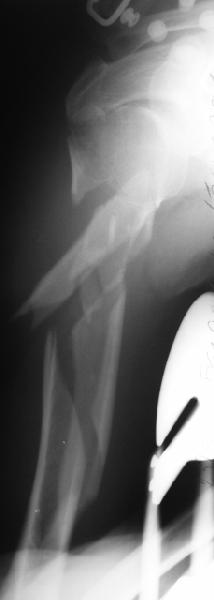

Well, to date he is still on abduction splint with traction applied to a wire placed through the olecranon. Images attached. The acetabulum

was ORIFed. The humerus is still discussing...

The views you now show demonstrate an extra articular fracture with good alignment on the AP, and some displacement on the lateral.

This should be able to be managed with adjustment of the traction.

Ilizarov is probably the best fixation if you decide to do so. However, it will heal with nonoperative treatment, with painless, reasonable

function. Even if it does not heal primarily, the pieces will heal enough to become a single level problem, readily solved with compression

plating. Jim Carr